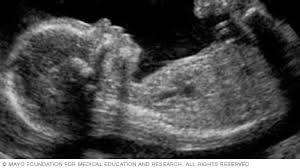

الموجات تلعب دورًا محوريًا في التشخيص والعلاج. على سبيل المثال، الموجات فوق الصوتية تعتمد على انتشار موجات صوتية عالية التردد داخل الجسم، حيث ترتد الموجات عند حدود الأنسجة المختلفة لتكوّن صورة حية للأعضاء الداخلية والجنين. كما تُستخدم الموجات الراديوية في التصوير بالرنين المغناطيسي لرصد الذرات داخل الجسم بدقة عالية. أيضًا، في العلاج، تُستخدم الموجات فوق الصوتية المركزة لتدمير الأورام أو تفتيت الحصى دون الحاجة للجراحة، مما يربط الفيزياء الطبية مباشرة بالتقنيات الحديثة للعلاج والتشخيص.